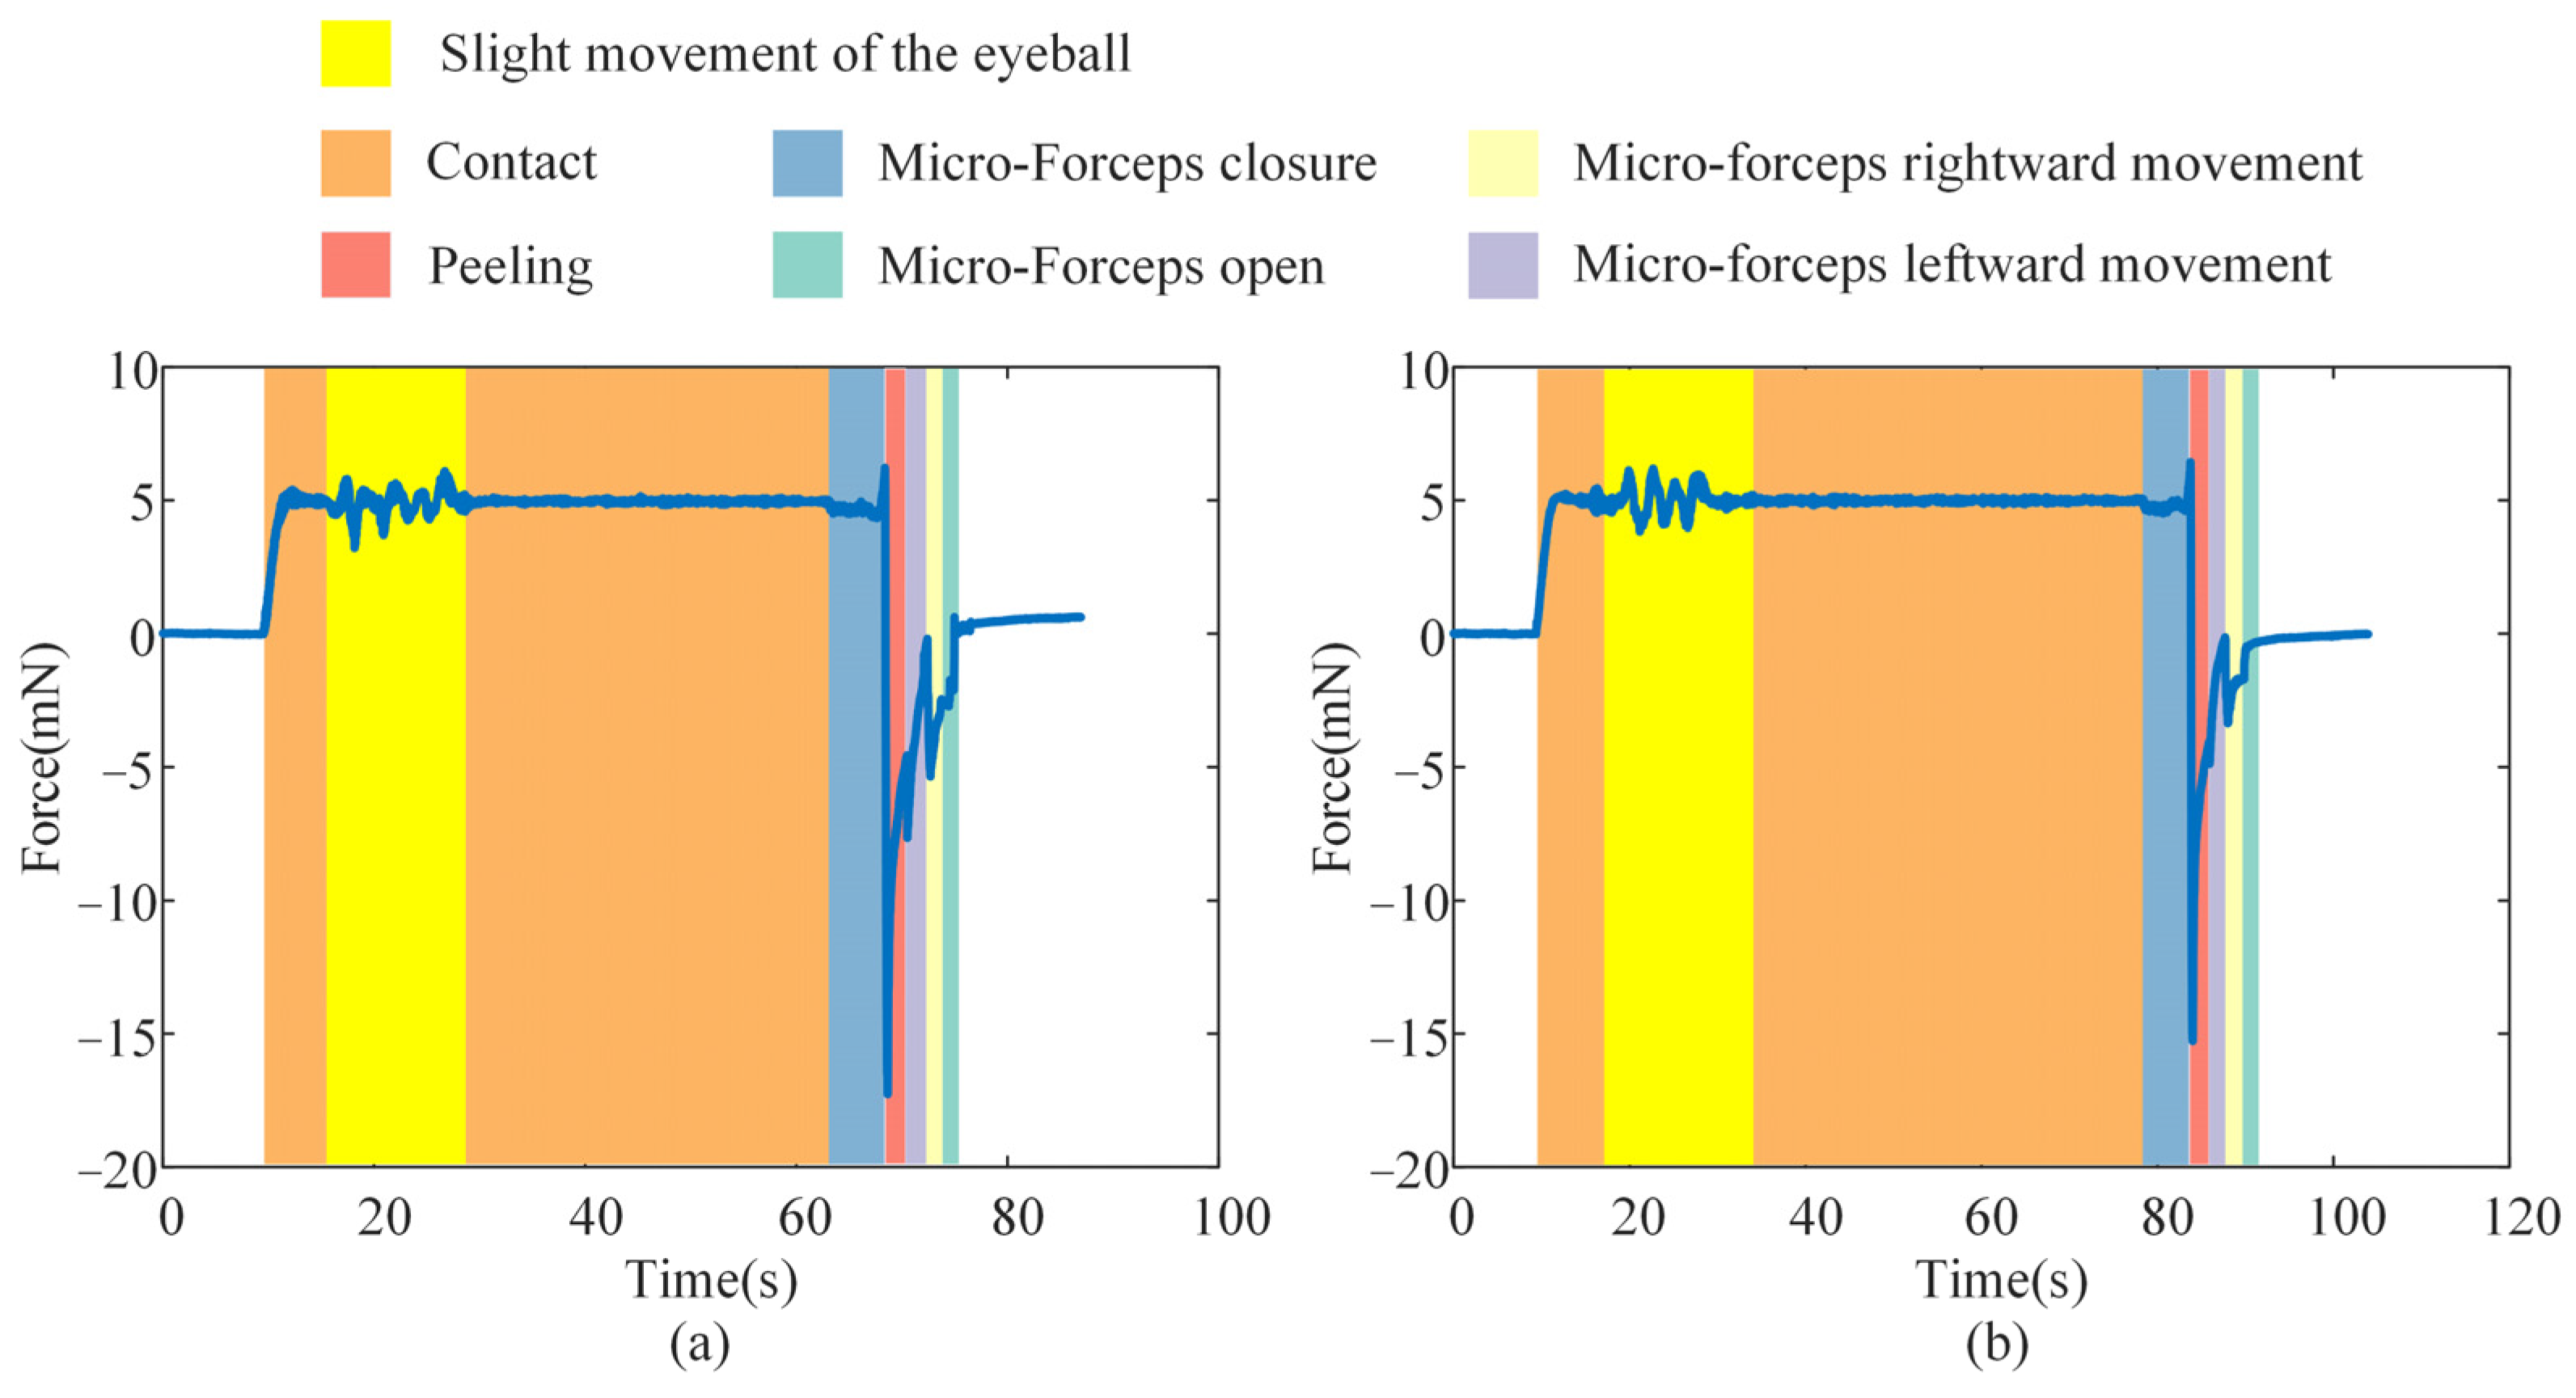

4.3. Break Initiation Experiment in ILM Peeling